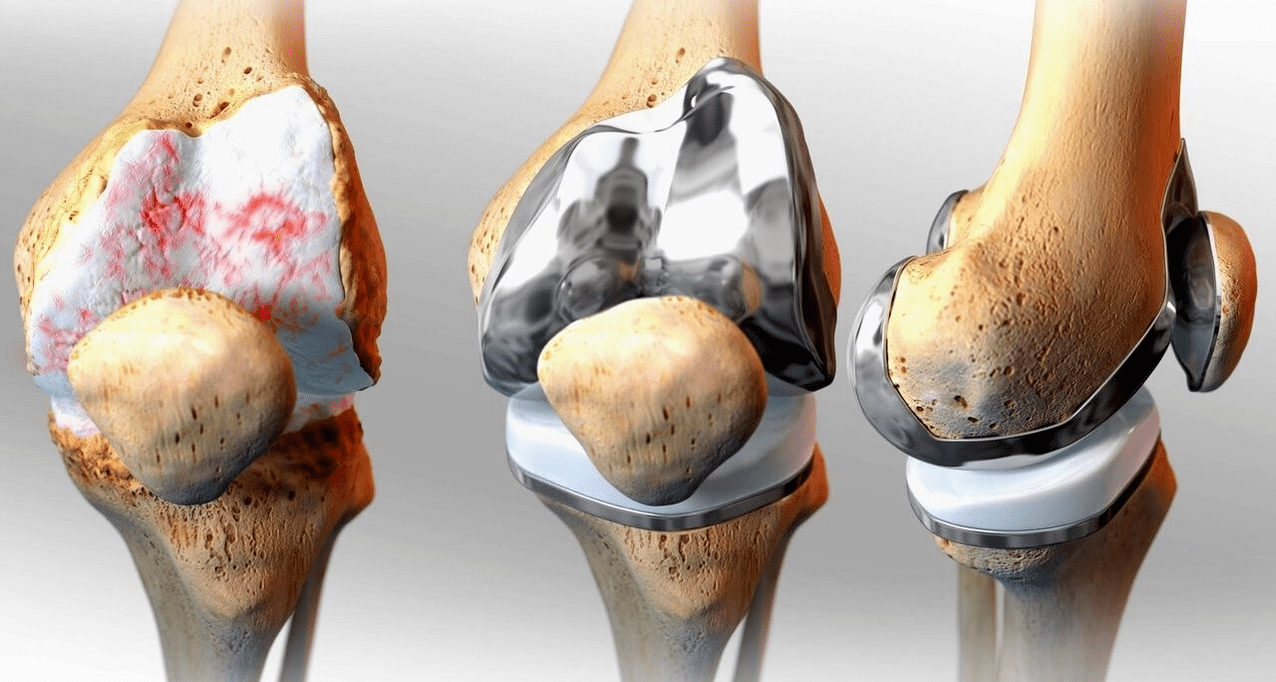

Traitement chirurgical et endoprothèses

Le remplacement par endoprothèse est une méthode chirurgicale courante et efficace pour traiter la gonarthrose sévère, vous permettant de maintenir la mobilité des membres et la capacité de mener ensuite une vie bien remplie. Il s’agit d’une opération high-tech qui dure environ une heure et demie. Dans la période postopératoire, une rééducation et un développement à long terme de l'articulation sont nécessaires. Après 25 à 30 ans, lorsque l'articulation artificielle s'use, elle doit être à nouveau remplacée.